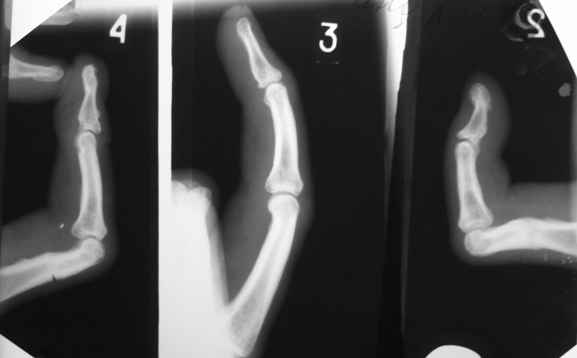

Для того, чтобы понять, действительно ли ПМФС находятся в подвывихе, надо сначала сделать четкую боковую рентгенографю сустава. Особенно это касается второго пальца. Да и на мониторе очень плохо видно состояние головки проксимальной фаланги 4 пальца. И что означает такой интересный объем движений в суставах? Объясните - существует ограничение только активных движений ( и каких?) или еще и пассивных?

Ограничение движений одинаковое и активных и пассивных. Движения в указанном объеме свободные. Чем вызвано ограничение понять пока не можем. В боковой проекции досняли - получается, что подвывиха нет. Вопросов, в отношении того, что мешает стало еще больше.

Насколько я понял - у больного имеется сгибательная контрактура 2-4 пальцев, то есть активное и пассивое сгибание этих пальцев практически полное. Но наблюдается ограничение пассивного и, тем более, активного разгибания пальцев, особенно 2 и 4 , в проксимальных межфаланговых суставах. Я так понял? Вы не указали, переломы были открытыми или закрытыми. Были ли повреждения сухожилий сгибателей или разгибателей? Если переломы были закрытые и если больного ну абсолютно не устраивает такое положение пальцев, то можно предложить следующие варианты. 1. Курс физиолечения плюс статические и динамические ( то есть с резиновой тягой) шины. Если больной это все получал и не отмечено положительного эффекта, то можно использовать второй вариант в различных модификациях. 1а- под проводниковой анестезией провести попытку редрессации, но не грубой, чтобы не поломать пальцы. Если редрессация не удается, то выполнить ладонную капсулотомию проксимального межфалангового сустава через 1-2 боковых поперечных разреза по нейтральным линиям пальца. Иногда приходится частично рассекать боковые связки. Опять попытка редрессации. Если снова ничего не получается, то следует обратить внимание на напряженный поверхностный сгибатель пальца. Этот сгибатель через эти же боковые разрезы нужно рассечь. Опять редрессация. Думаю, что в последнем случае Вам повезет. Уффф!

Да, забыл. Третий палец я бы вообще не трогал или ограничился только лишь небольшой редрессацией ( насколько я понял по картинкам и описанию - ограничение пассивно-активной функции на 3 пальце - абсолютно минимальные).